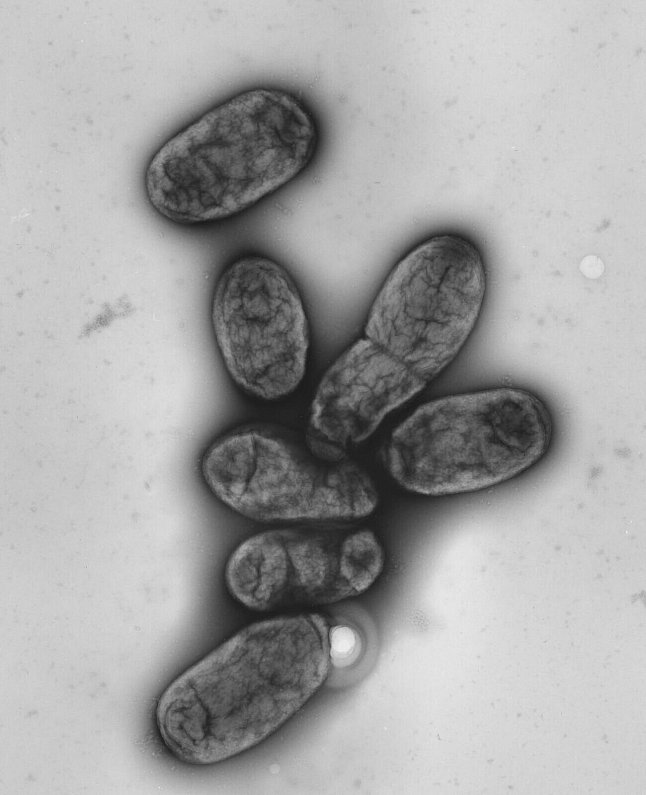

Das Pestbakterium Yersinia pestis - © picture alliance / dpa

Das Pestbakterium Yersinia pestis | © picture alliance / dpa